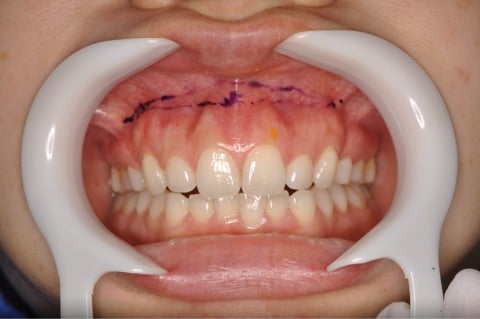

<ガミースマイルの切開ライン>

▶︎メスによるガミースマイル手術の場合出血が多くなる傾向があったり、局所麻酔を行ったにしても

何となく切られている感覚があり、恐怖感が出やすい手術です。

当院のレーザーを使用した手術では術中はパチパチとした音と水が出るだけで切られている感覚はありません。

また、術後の腫れに関してもメスで切ることに比べるとレーザーの方が腫れにくいと言われています。

(※個人差があるので腫れる事は腫れます。その場合も2〜3日程度で落ち着くでしょう。)

術後も不要な出血が無く、約1時間程度で手術が可能です。